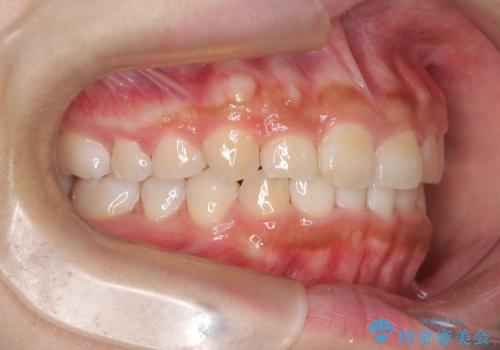

目立たない矯正で中等度の叢生を改善

- 歯のデコボコ(叢生)を気にされて来院されました。精密な検査の結果、中等度の叢生と診断。患者様のご希望に合わせ、透明で目立ちにくい**インビザライン(マウスピース矯正)**による治療計画を立案しました。歯を抜かずに、歯列弓(歯が並ぶアーチ)を少しずつ拡大することで、歯が並ぶスペースを確保し、叢生を改善することを目指します。

今回の矯正治療では、透明なマウスピース型の装置インビザラインを使用しました。この装置は目立ちにくく、取り外しが可能なため、食事や歯磨きも普段通りに行えます。治療は、緻密に計算された治療計画に基づき、段階的に作製されたマウスピースを交換していくことで、歯列弓全体を徐々に広げていきました。この歯列弓の拡大により、不足していたスペースを確保し、歯のデコボコを効果的に解消。抜歯することなく、整った美しい歯並びと良好な咬み合わせを獲得していただけました。